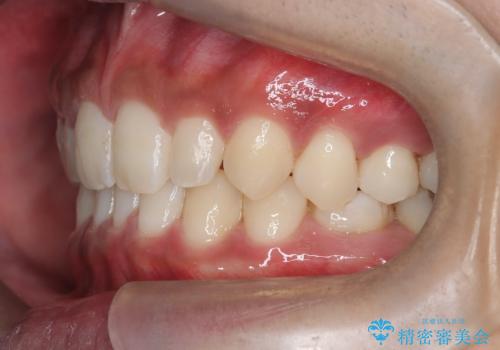

【インビザライン】空隙歯列の矯正

- 前歯の隙間を主訴に来院されました。

なるべく目立たない治療を希望されましたので、インビザラインにて治療を行なっております。

単純に前歯の隙間の閉鎖をしてしまうと、前歯に早期接触が生まれ、臼歯が噛まなくなってしまいます。適切な治療計画を立てることで、噛み合わせも良好な結果を得ることができました。